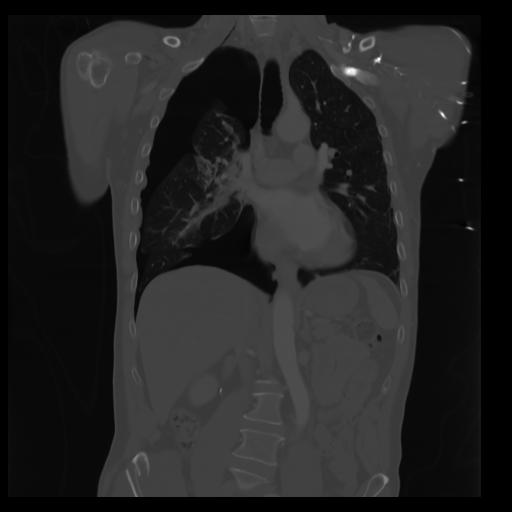

29 CUERPO,CE,Coronal,3.000,CUERPO,Coronal,